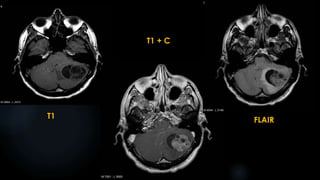

T2WI

T1WI

T1 + C

DWI

FLAIR

Differential diagnosis:

 Ganglioglioma

 Pleomorphic xanthoastrocytoma

 Pilocytic astrocytoma

 Desmoplastic infantile ganglioglioma

 Oligodendroglioma

 Choroid fissural cyst

 HSE and limbic encephalitis

 Mesial temporal sclerosis